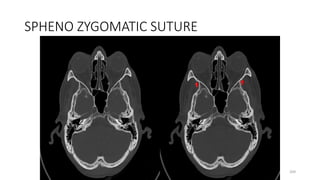

SPHENO ZYGOMATIC SUTURE